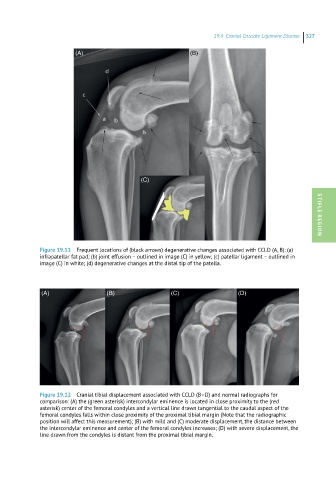

Figure 19.11 Frequent locations of (black arrows) degenerative changes associated with CCLD (A, B): (a) STIFLE REGION

infrapatellar fat pad; (b) joint effusion – outlined in image (C) in yellow; (c) patellar ligament – outlined in

image (C) in white; (d) degenerative changes at the distal tip of the patella.

Figure 19.12 Cranial tibial displacement associated with CCLD (B–D) and normal radiographs for

comparison: (A) the (green asterisk) intercondylar eminence is located in close proximity to the (red

asterisk) center of the femoral condyles and a vertical line drawn tangential to the caudal aspect of the

femoral condyles falls within close proximity of the proximal tibial margin (Note that the radiographic

position will affect this measurement); (B) with mild and (C) moderate displacement, the distance between

the intercondylar eminence and center of the femoral condyles increases; (D) with severe displacement, the

line drawn from the condyles is distant from the proximal tibial margin.